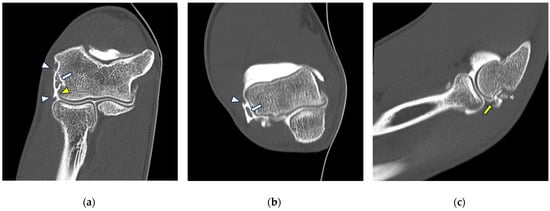

Figure 8.

CT arthrography of a patient with lateral epicondylitis subjected to multiple corticosteroid injections. (a,b) Coronal and axial images show extravasation of intra-articular contrast into lateral periarticular soft tissues through a large full-thickness tear of both the radial collateral ligament and the proximal common extensor tendon (white arrowheads). Diffuse thinning of radial head dish cartilage is also displayed (white arrows); (c) sagittal image also shows distal displacement of the annular ligament (yellow arrowhead) and cartilage fraying of the radial head side (yellow arrow).